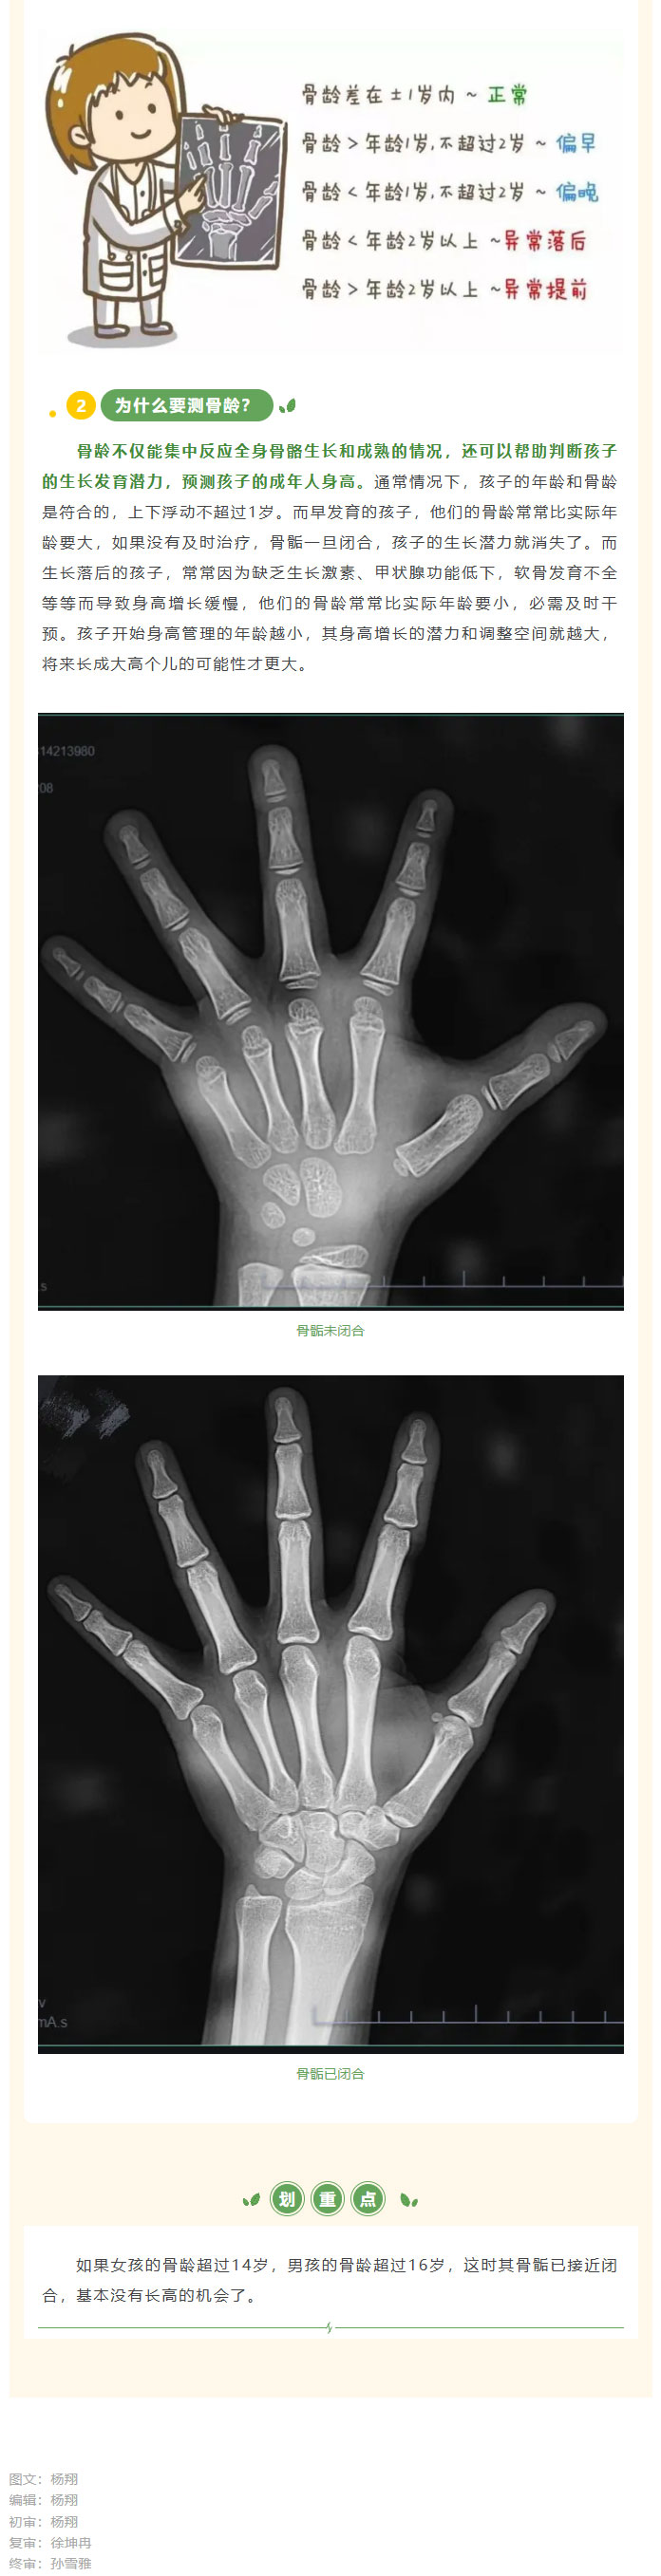

商城县人民医院儿科免费测骨龄活动开始啦!01.jpg商城县人民医院儿科免费测骨龄活动开始啦!02.jpg